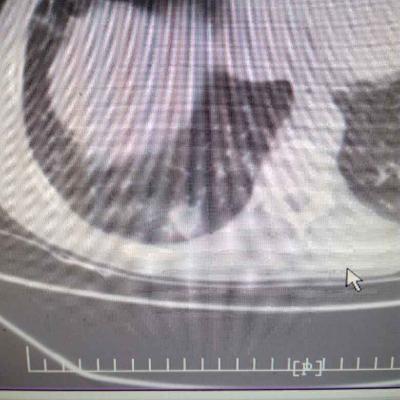

1.胃食管反流病 1.1反流性食管炎LA-B 2.食管裂孔疝 处理:患者诊断明确,行腹腔镜下食管裂孔疝修补术+胃底折叠术。

患者术后一周出院,反酸、烧心、嗳气症状明显缓解,无吞咽不畅等症状。 讨论:对于诊断有食管裂孔疝病人的胃食管反流病,且用药有一定疗效,建议行手术治疗,行腹腔镜下食管裂孔疝修补术,修补了膈裂孔,同时行胃底折叠术,加紧了贲门括约肌压力,共同形成抗“反流瓣”。